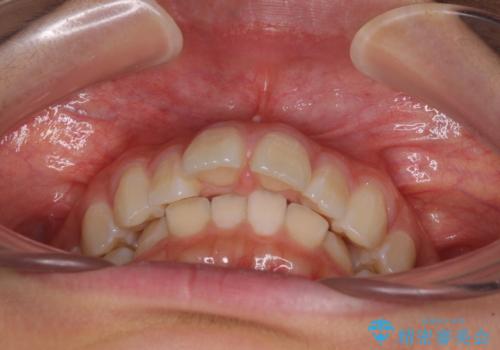

深い咬み合わせで前方に煽られた前歯 高校生のインビザライン矯正治療

- 前歯の隙間と前方に飛び出していることを気にして来院された患者様です。

奥歯の咬み合わせを見ると、上顎が下顎に対して相対的に前方にありました。

咬み合わせも深くなっていたため、上顎臼歯を後方に移動させつつ、下顎の小臼歯を直立させ、奥歯の咬み合わせを改善する必要があります。

インビザライン単体で対応することも検討できますが、達成する可能性が低いため、カリエールディスタライザーという補助装置を併用して、より確実性を上げることとしました。